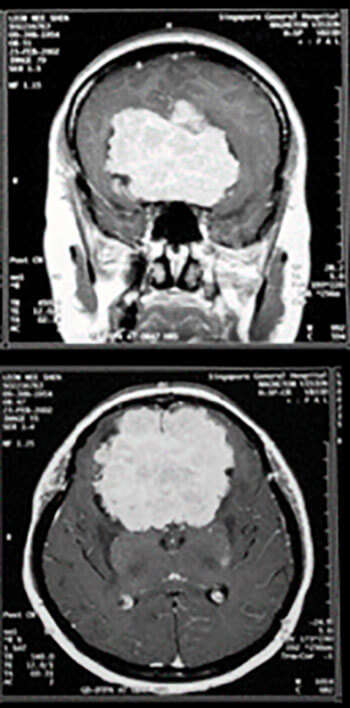

Figure 3: Brain MRI coronal (A) and axial (B) images showing a huge frontal meningioma.

Figure 4: Brain MRI with contrast showing a large infiltrating frontal

glioma involving both hemispheres, most likely a GBM.

Astrocytomas comprise up to 50% of primary brain tumours and can originate anywhere in the brain parenchyma, often presenting with seizures; the more benign varieties are commonest in the fourth decade of life but the GBM is usually seen in the fifth or sixth decade (Figures 4 and 5).